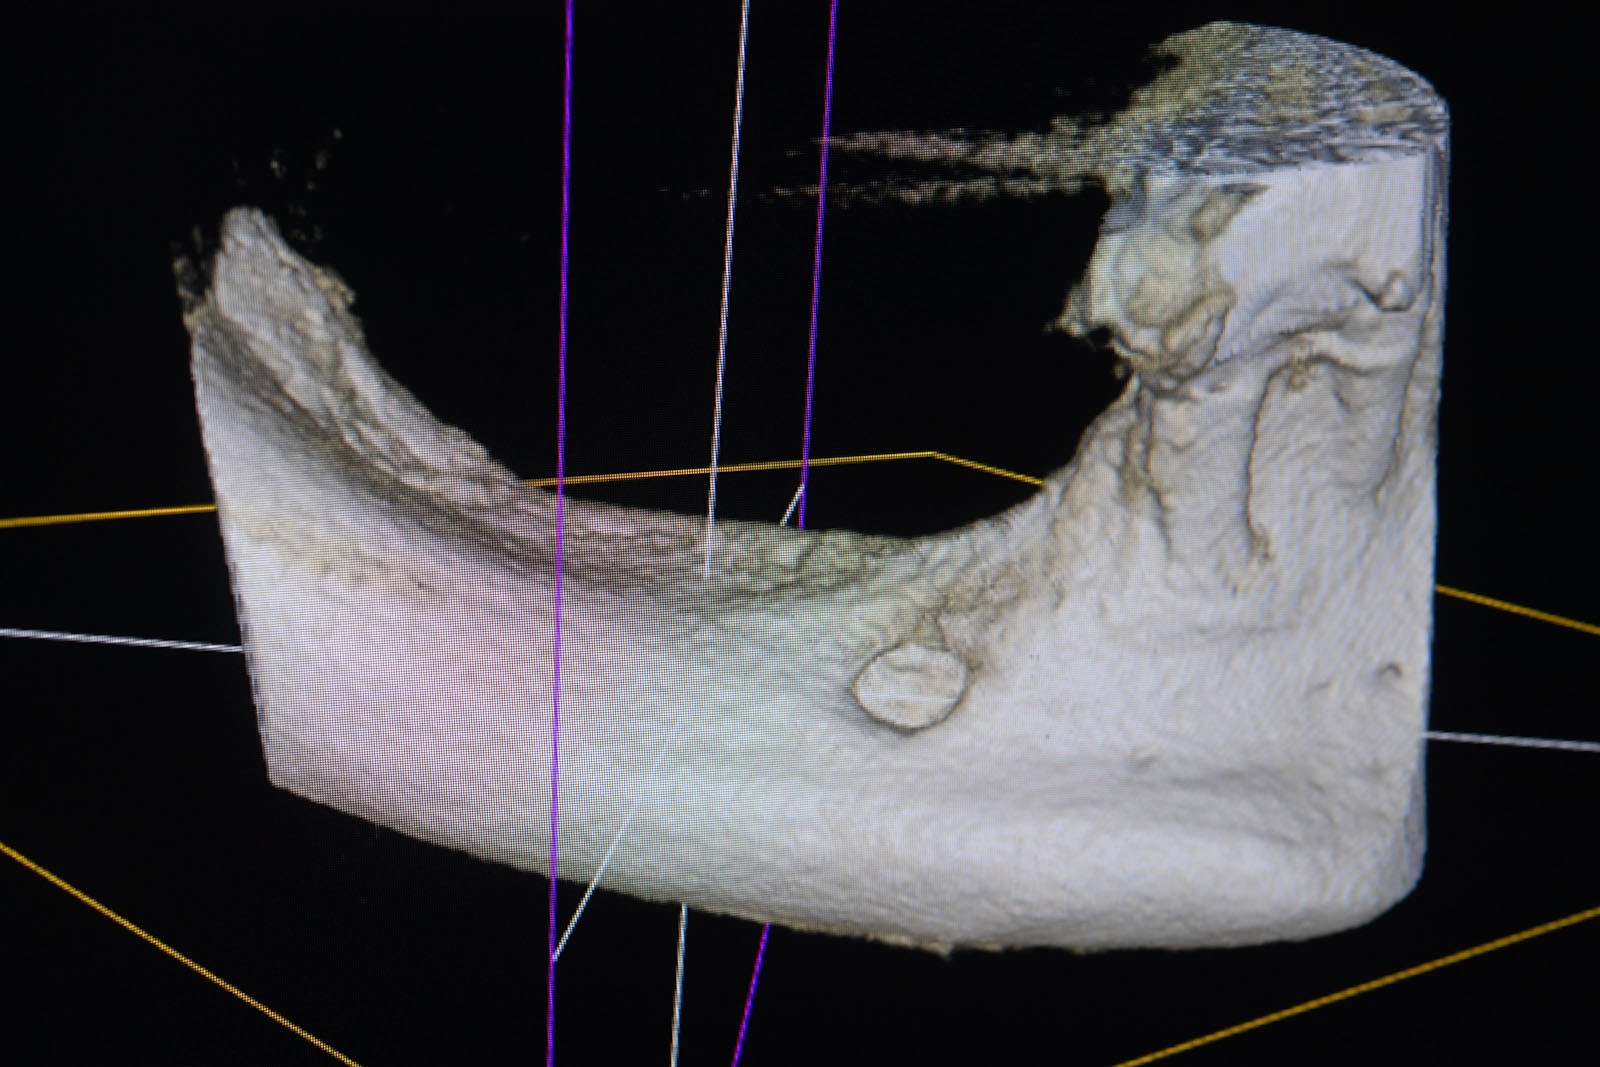

Przed podjęciem leczenia należy określić stopień zaniku kości szczęk oraz żuchwy. W tym celu przeprowadza się badanie kliniczne oraz odpowiednią diagnostykę obrazową pacjenta. Uwzględnia ona zdjęcie panoramiczne OPG jako podstawę dwuwymiarowego obrazowania podłoża kostnego oraz możliwe jest badanie tomograficzne CT lub bardziej precyzyjna tomografia stożkowa CBCT. Opcjonalnie wykorzystywana diagnostycznie tomografia pozwala na bardziej wnikliwą ocenę stopnia zaniku kości w trójwymiarowym, przestrzennym obrazie.

To kolejna metoda umożliwiająca precyzyjną odbudowę zadanego kształtu tkanki kostnej przy użyciu standardowych materiałów kościotwórczych, kości własnej lub PRF oraz zewnętrznego rusztowania w postaci siatki z biozgodnego stopu tytanu. Siatka jest indywidualnie projektowana w technologii CAD CAM i następnie drukowana dla konkretnego przypadku.

Dotychczas stosowane stabilizatory zewnętrzne w formie siatek tytanowych używane do regeneracji kostnej lub w zabiegach odtwórczych w chirurgii szczękowo-twarzowej uwzględniały materiały ręcznie doginane i formowane podczas zabiegu operacyjnego. Zastosowanie technologii CAD CAM dla potrzeb druku materiałów przeznaczonych do indywidualnej rekonstrukcji kostnej znacznie poprawiło precyzję i jakość uzyskiwanych efektów. Wdrożenie biozgodnych stopów tytanu do druku siatek zdecydowanie ograniczyło odsetek powikłań zapalnych.

Siatki stanowią stabilną obudowę – ograniczenie nadające kształt regenerowanej kości przy użyciu upakowanego pod nią materiału. Utrzymują i stabilizują rozdrobniony granulat kościotwórczy, co jest warunkiem prawidłowego procesu gojenia, jednocześnie nadając anatomiczny kształt i zakres odbudowie kostnej sprzed jej zaniku.

Precyzja projektu druku siatki bazuje na dokładności odwzorowania kształtu kości w stożkowej tomografii komputerowej CBCT, co zapewnia ich dobre przyleganie do podłoża kostnego oraz ogranicza powstawanie powikłań w postaci obnażania się siatek.